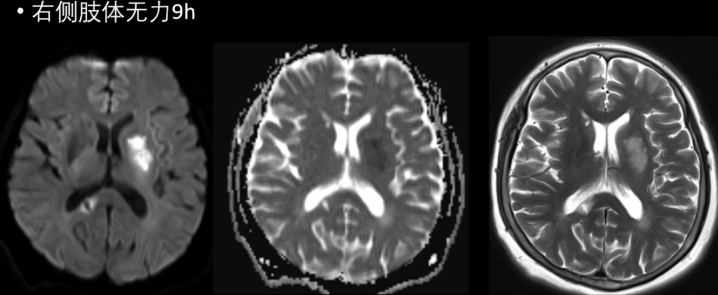

(1)超急性期(<6h):CT 及 MRI 检查阴性,DWI 呈明显高信号。

(2)急性期(6-72h):CT 表现低密度区,MR 表现长 T1 长 T2 异常信号,DWI 呈较明显高信号。

发病机制为从一侧大脑后动脉 P1 段发出一条主干动脉(Percheron动脉)闭塞所致,该动脉分支供应双侧丘脑(如下图可见解剖学示意图)。

病因脑小血管病、心脏疾病、大动脉疾病等。

典型临床表现意识障碍、垂直注视麻痹、记忆力缺损三联征。

影像学表现:双侧丘脑、中脑长 T1 长 T2 信号;中脑“V”字征。